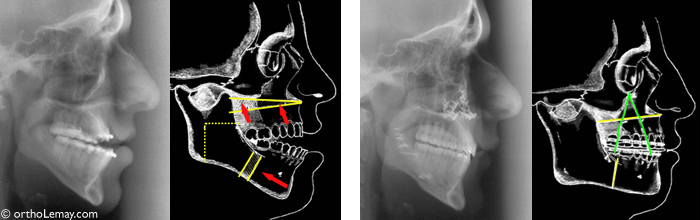

Radiographies avant et après la chirurgie et diagrammes illustrant les mouvements effectués sur les mâchoires dans un cas de classe 3 avec béance antérieure.